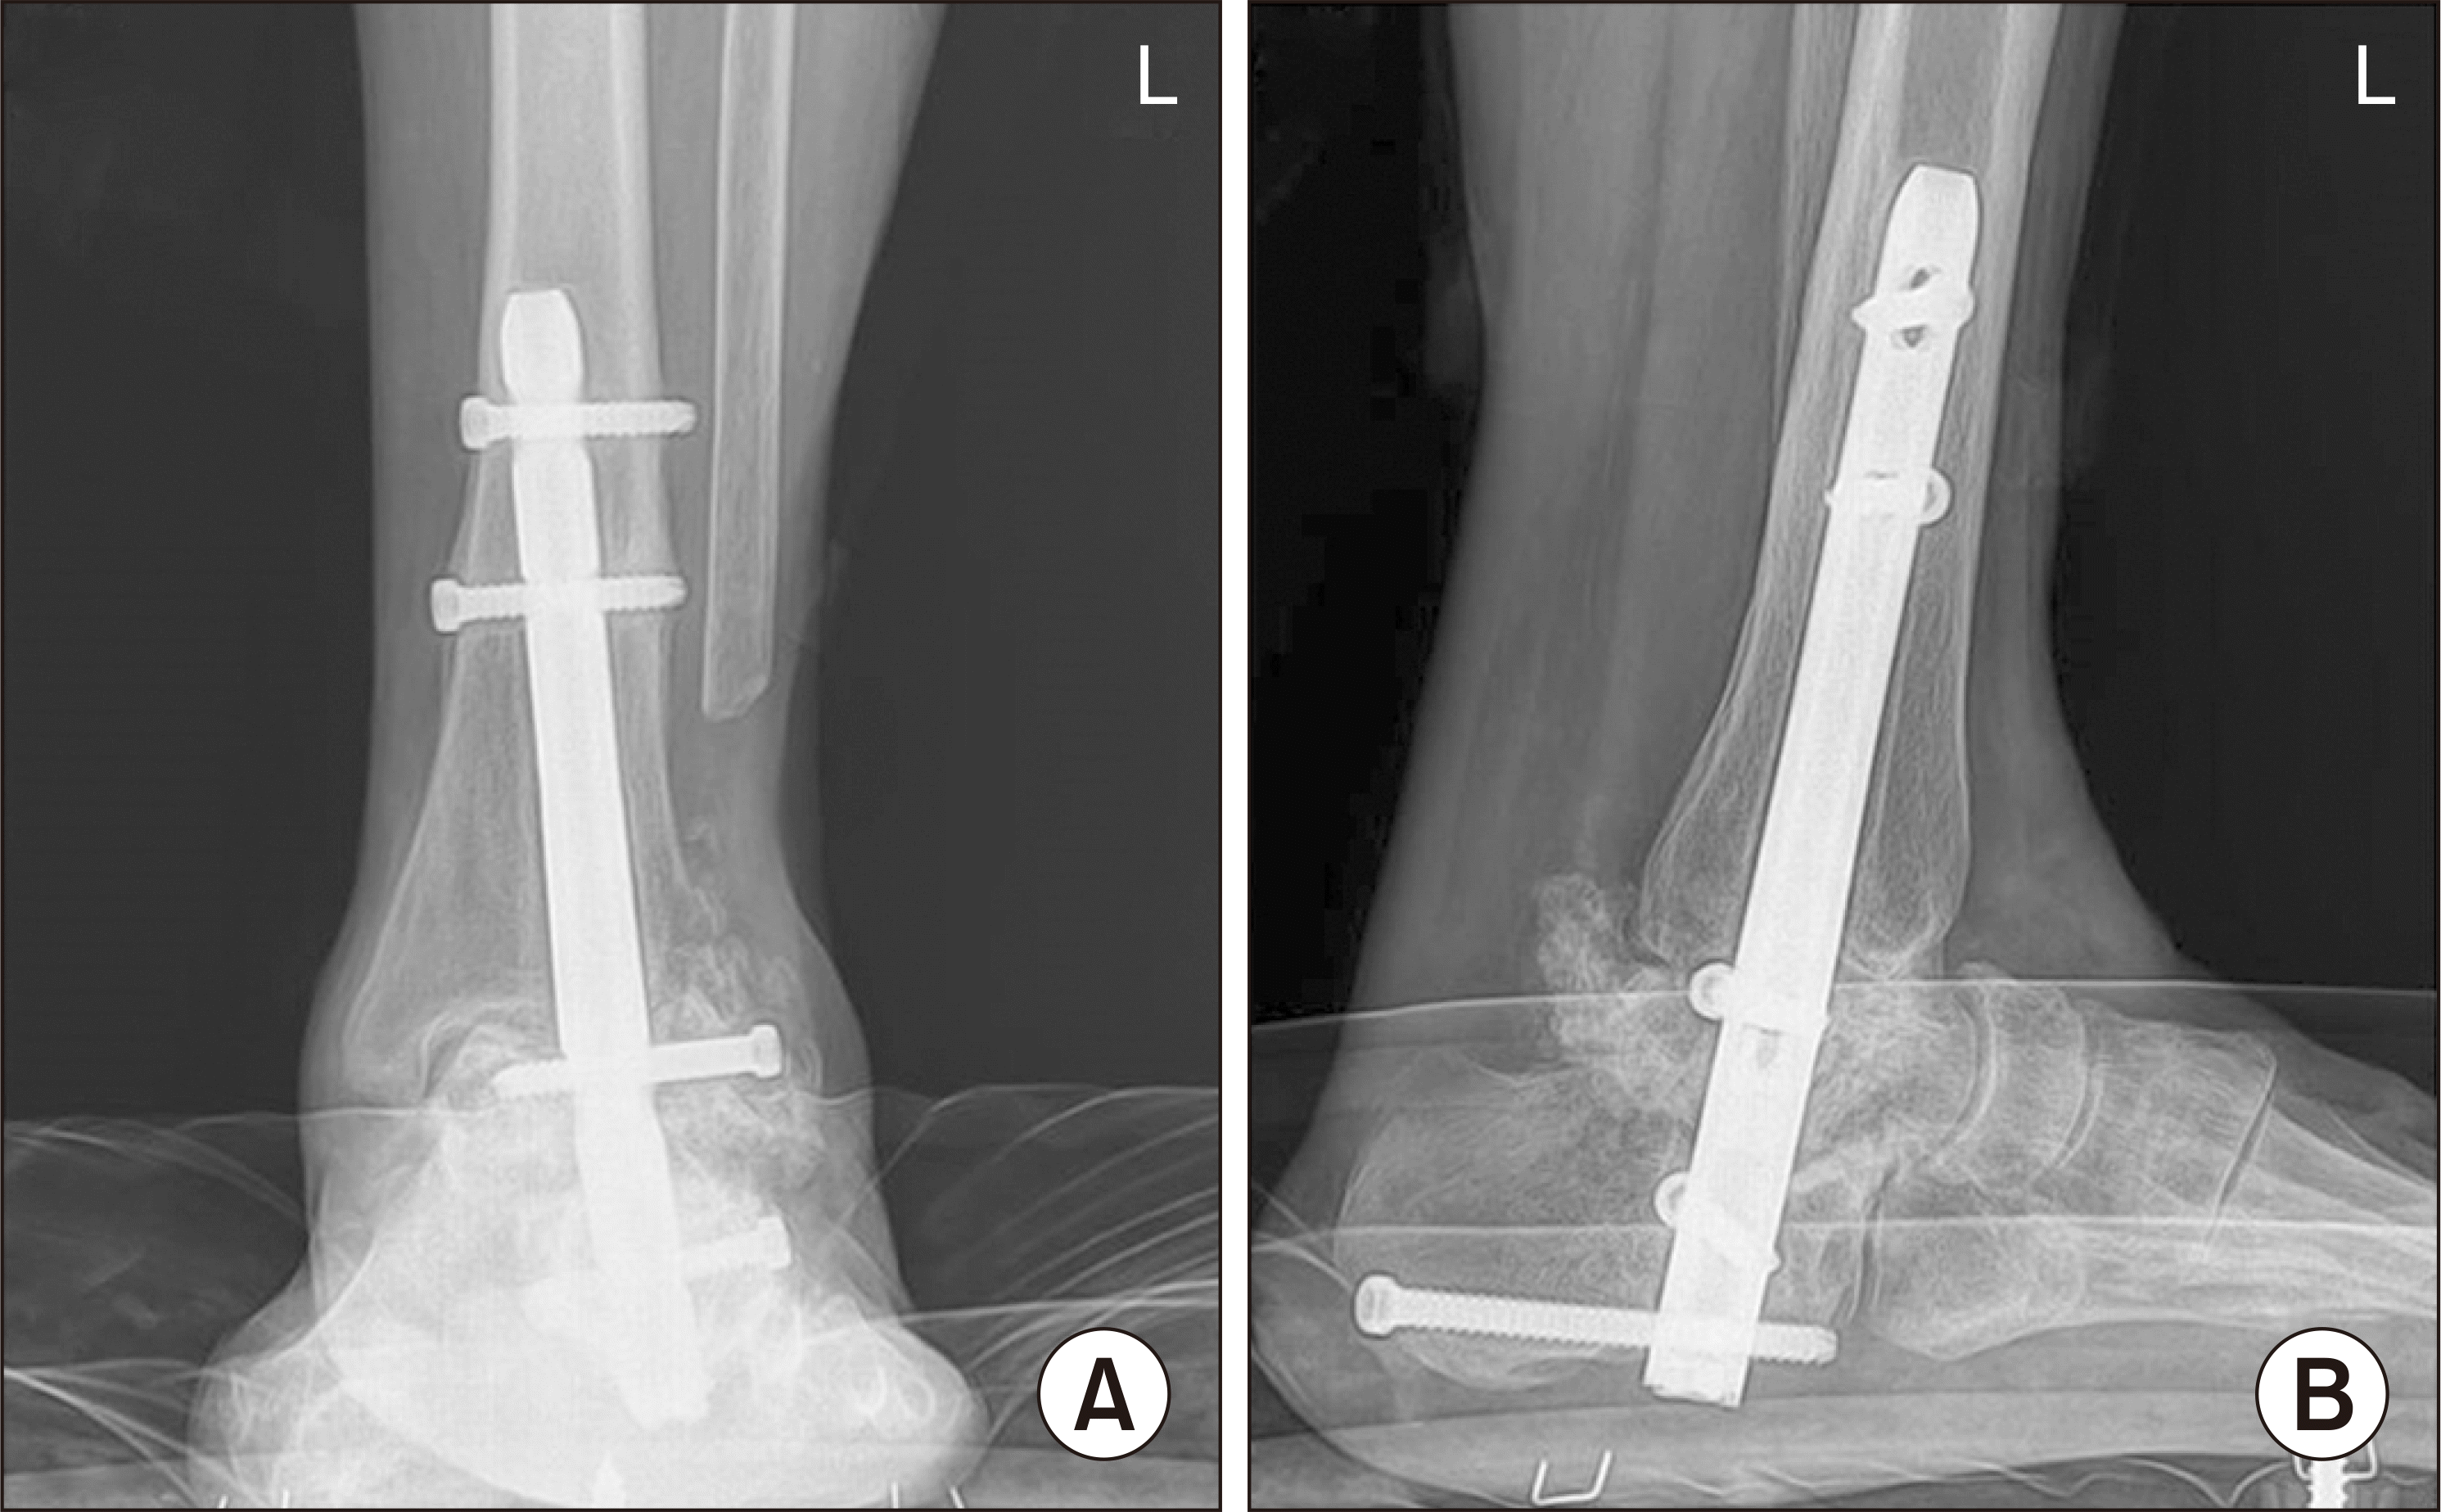

66세 여자 환자가 약 10년 전부터 특이 외상력 없이 발생한 좌측 족관절의 통증 및 부종을 주소로 내원하였다. 환자는 약 50년 전의 결핵 외의 특이 과거력은 없었다. 환자는 내원 5년 전부터 수년간에 걸쳐 좌측 족관절에 금침을 맞은 이력이 있었으나 음주, 흡연력은 없었고 스테로이드 치료를 받은 적은 없었다. 환자는 내원 1년 전부터 서서히 증상이 악화되었고, 내원 당시 시행한 이학적 검사에서 좌측 족관절의 전반적인 압통 및 경도의 부종이 있었다. 혈액 검사상 백혈구 수 4,000개/mm3, 적혈구 침강 속도 21 mm/hr, C-반응 단백 0.2 mg/dL의 정상 소견을 보였고 초음파를 이용한 족관절의 관절액 검사에서도 특이 소견이 없었으며 균 배양 검사는 음성 결과가 나왔다. 기립 발목 radiograph에서 거골의 침강 및 거골하 관절염 소견을 보였으며 자기공명영상(magnetic resonance imaging)에서 관절 부종을 동반한 좌측 거골 및 종골의 진행된 골파괴 소견이 관찰되어(Fig. 1), 거골의 골괴사 진단 하에 동종 거골을 이용한 경거종골 유합술을 계획하였다.

환자는 수술 후 1주째 특이 합병증 없이 퇴원하였고 수술일로부터 6주간 비체중부하 및 단하지 석고고정술을 시행하였다. 수술 중 시행한 연부조직 및 골조직의 세균 배양 검사는 음성으로 결과가 나왔다. 이후 추시 전기간 동안 감염, 임플란트로 인한 불편감 등의 합병증은 발생하지 않았다. 환자 수술 후 2년째 외래 추시에서 수술 전 8점이었던 visual analogue scale score가 1점으로 감소하였고 증상의 호전과 함께 radiograph에서 경거종골 관절의 유합이 확인되었다(Fig. 5). 2년 추시 radiograph에서 수술 직후 radiograph에 비하여 경거종골 관절의 5 mm 높이 소실이 관찰되었으나 환자는 이로 인한 불편감을 따로 호소하지 않았다.